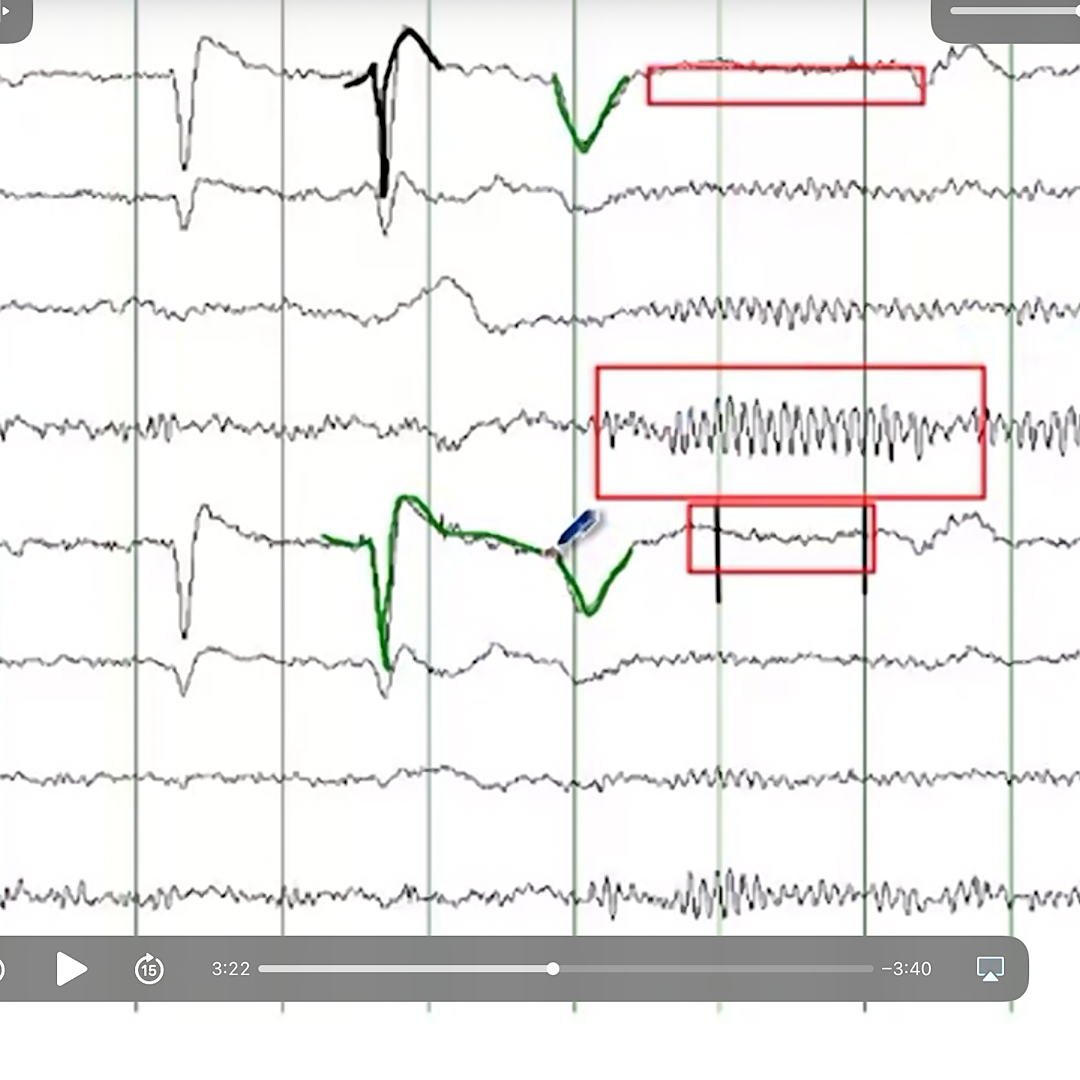

What does the downward green angle in the frontal head region represent?

Eye closure

Diagnosis?

Centro temporal spikes

as seen in benign rolandic epilepsy

(different example below)